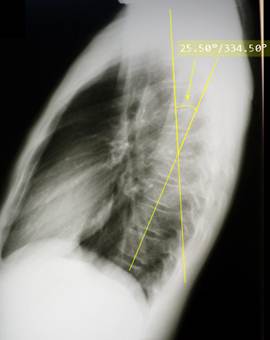

Боковая

рентгенограмма позвоночника здорового ребенка 8 лет. Обратите внимание, что начали

прослеживаться тени ядер окостенения апофизарных колец (некоторые из них

отмечены зелеными стрелками). Форма тел верхних грудных позвонков очевидно клиновидная, причем угол

клиновидности составляет 5 – 7 градусов. Тела нижних грудных позвонков имеют

несколько овоидную форму с отчетливым сужением кпереди. Подобная картина является нормальным явлением

для детей в возрасте 8 – 12 лет. При выставлении диагноза компрессионного

перелома тела позвонка следует опираться

не только на рентгенологическую картину, но и на данные анамнеза и клинического

осмотра.

Компрессионный

перелом 9 и 10 грудных позвонков у девочки 16 лет, получившей кататравму –

падение со второго этажа. Клиновидность тела десятого грудного позвонка

составляет 15 градусов, девятого – 9 градусов. Пострадавшая жаловалась на

сильнейшие боли в спине при постукивании в области остистых отростков этих

позвонков, а также при любых движениях.

Диагноз компрессионного перелома тел 9 и 10 грудных позвонков не

вызывает сомнений. Удивительно, но никаких других повреждений, кроме обширного осаднения кожи спины и левого

бедра, больше не обнаружилось.